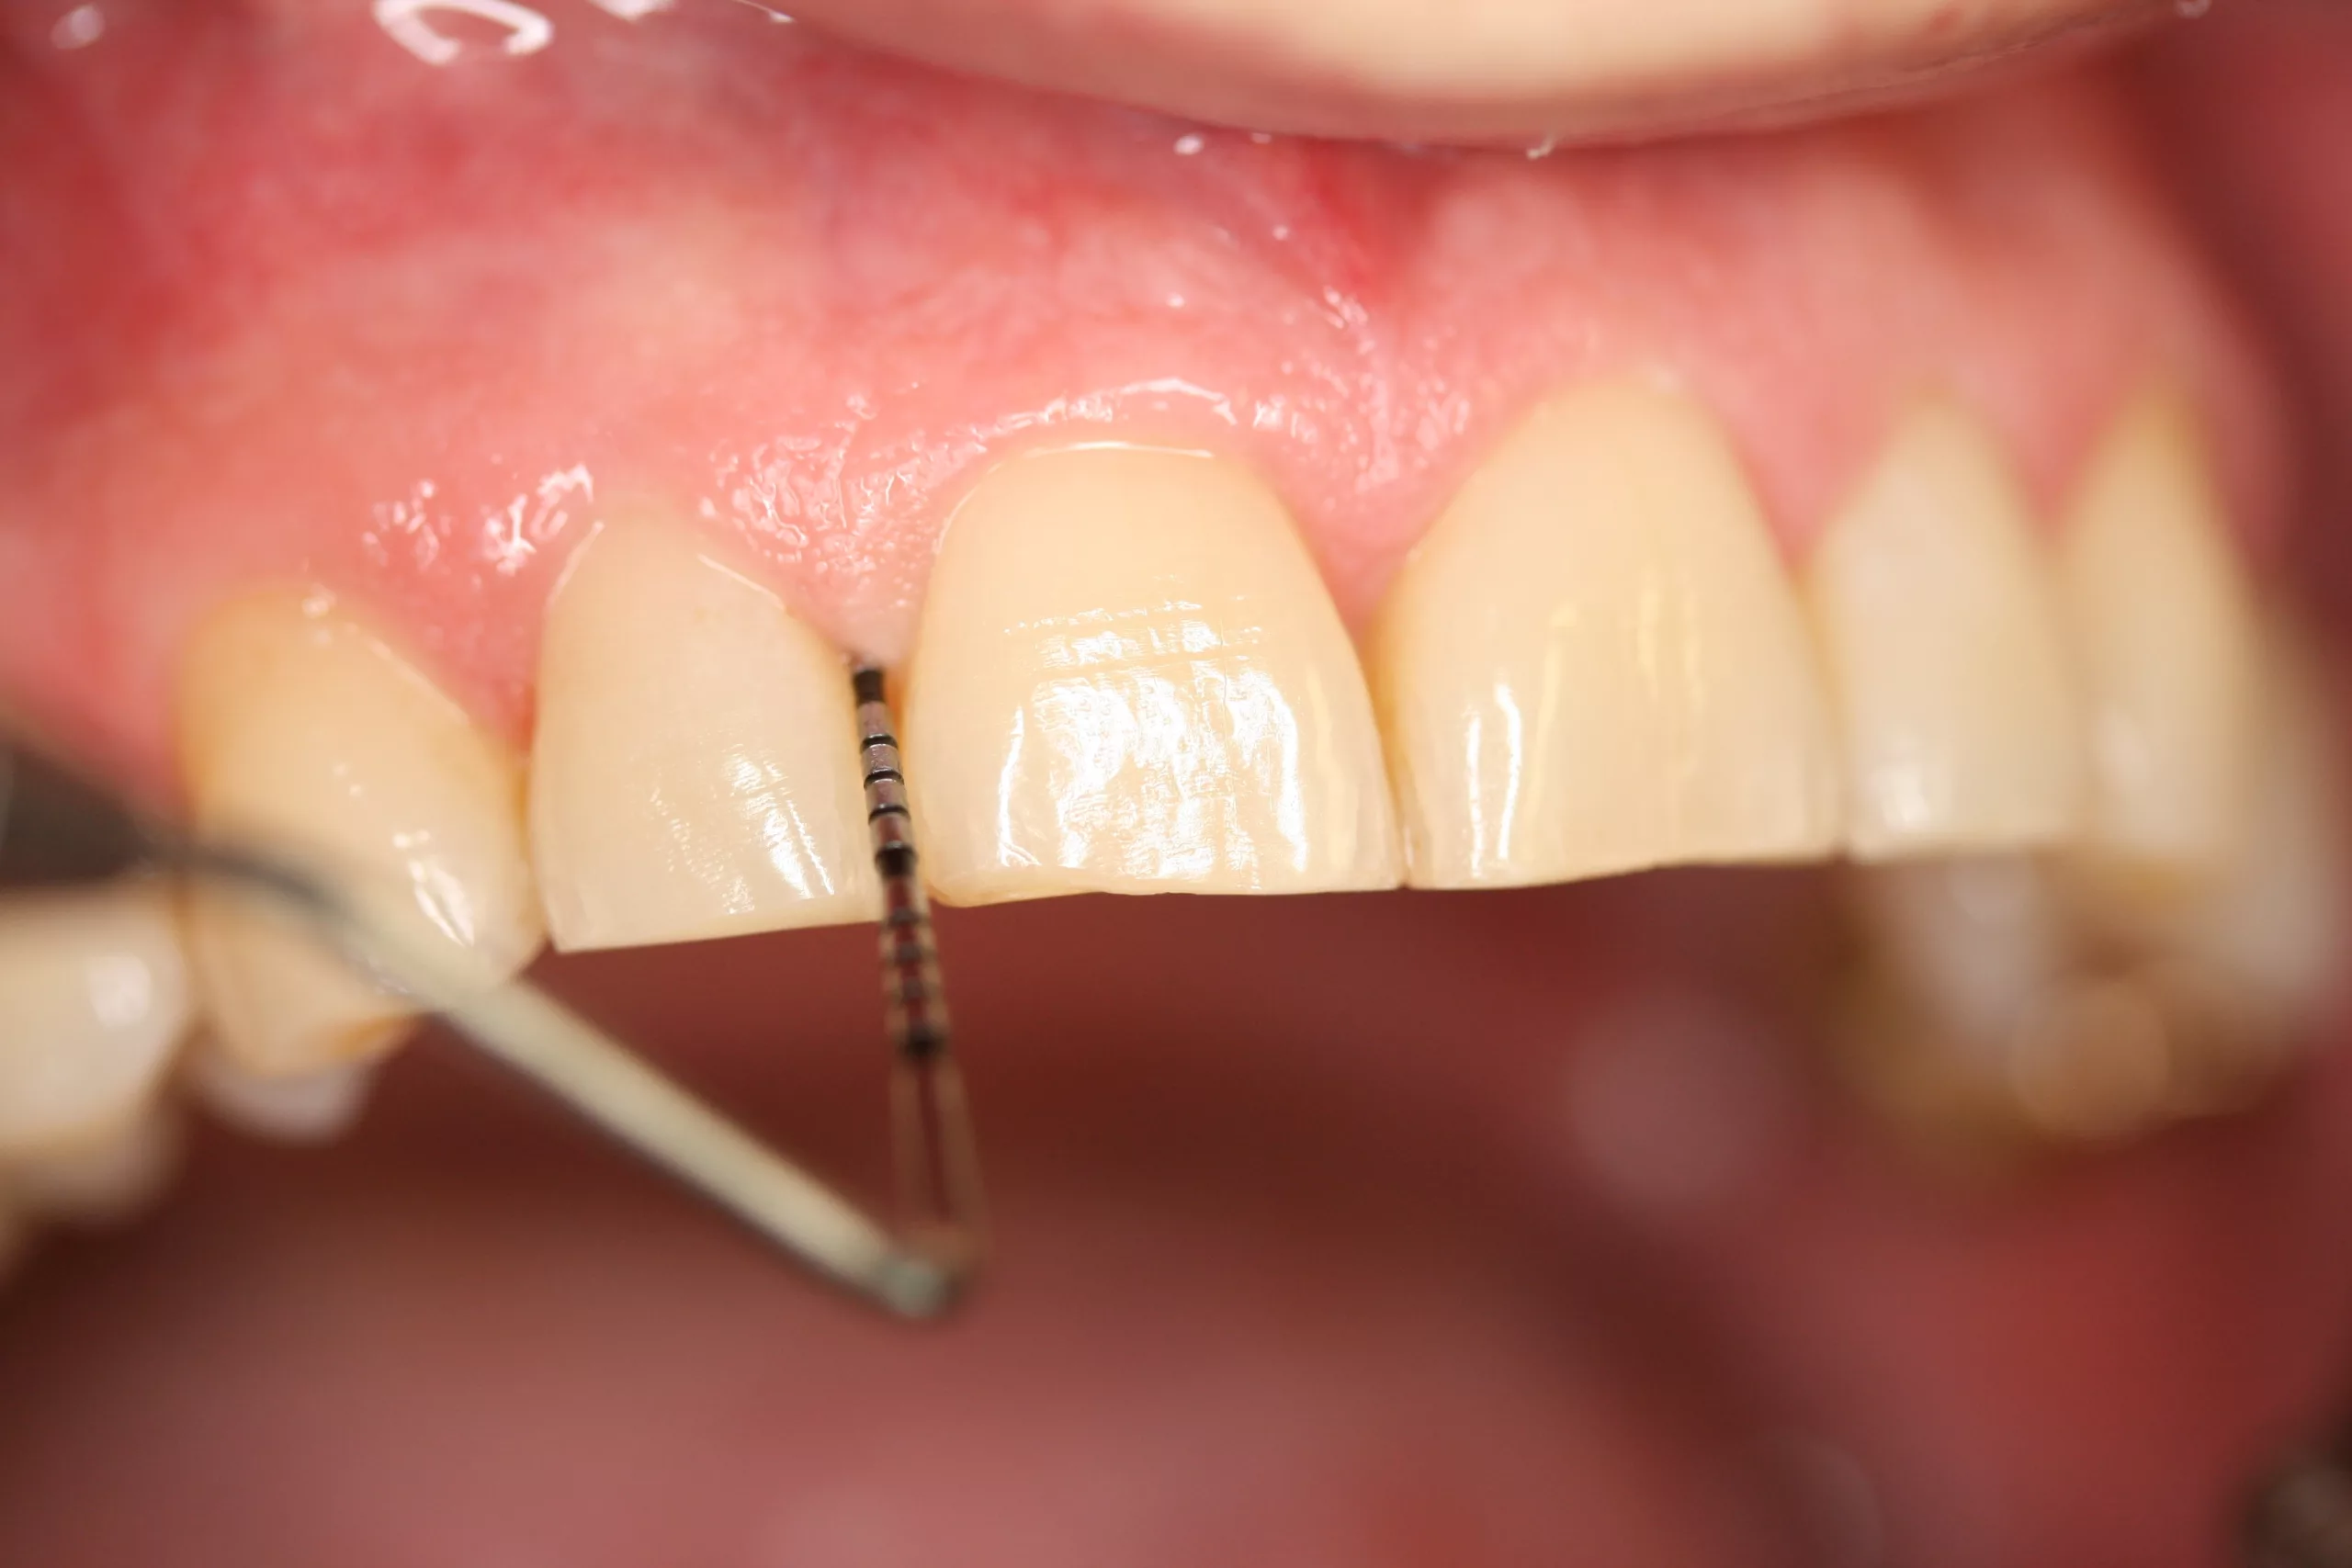

Als Parodontitis marginalis bezeichnet man eine komplexe, chronisch- entzündliche parodontale Erkrankung, die bei anfälligen Individuen von Bakterien eines dysbiotischen oralen Plaque-Biofilms ausgelöst wird. Die Entzündung der parodontalen Gewebe zeigt sich klinisch primär als Rötung und/oder Schwellung der marginalen Gingiva. Beim Sondieren der sulkulären Gingiva sind Blutungen und Sondiertiefen > 3 mm feststellbar. Bei der bakteriellen Infektion werden bindegewebiges parodontales Attachment und alveolärer Knochen zerstört. Die fortschreitende parodontale Zerstörung reduziert die Stabilität der erkrankten Zähne, die sich zunehmend lockern und ohne adäquate Behandlung letztendlich verloren gehen können [2].

Zum Timing der Nachsorge von Implantaten existieren keine systematischen Langzeitstudien vergleichbar denen bei Zähnen. Es ist jedoch bekannt, dass Mukositis und Periimplantitis häufig auftreten. So stellte eine umfangreiche systematische Reviewstudie und Metaanalyse bei 63% der Implantatpatienten Mukositis fest, von der mehr als 30% der Implantate betroffen waren. Nahezu 20% der Patienten litten an einer Periimplantitis, von der ca. 10% der Implantate betroffen waren [13]. Zudem schreitet der Knochenabbau bei Periimplantitis meist rascher fort als bei Parodontitis. Deshalb sollte die Häufigkeit der Implantatnachsorge mindestens der von Zähnen entsprechen. Das bedeutet: Wenn ein Implantat einen Zahn ersetzt, der aufgrund von schwerer Parodontitis verloren ging, sollte das Recallintervall 3 Monate betragen. Falls die Implantation aus nichtparodontalen Gründen erfolgte, reicht wohl ein Termin alle 4 (bis maximal 6) Monate aus. Beim Timing der Nachsorge sind lokale und systemische Risikofaktoren zu berücksichtigen [13]. Bei Rauchern beispielsweise treten Mukositis und Periimplantitis deutlich häufiger auf als bei Nichtrauchern [14].